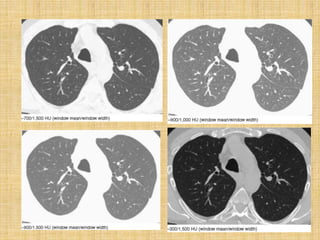

    At least one consistent lung window setting is

necessary. Window mean/width values of -600 HU to -

700 HU/1,000 HU to 1,500 HU are appropriate. Good

combinations are -700/1,000 HU or -600/1,500 HU.

Soft-tissue windows of approximately 50/350 HU

should also be used for the mediastinum, hila, and

pleura.

    Windows: Windows may need to be customized; a low-

window mean (-800 to -900 HU) is optimal for

diagnosing emphysema. For viewing the mediastinum,

50/350 HU is recommended. For viewing pleuro-

parenchymal disease, -600/2,000 HU is recommended.